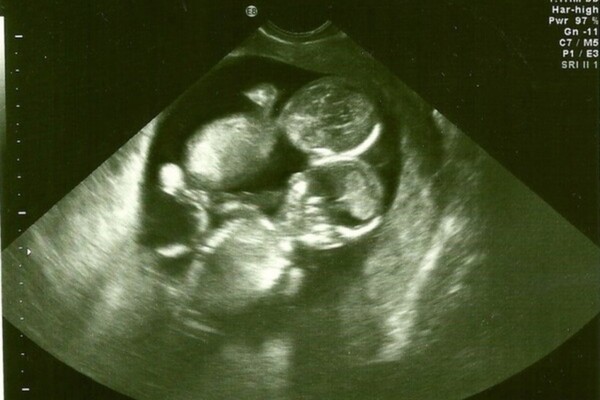

Tuy nhiên, niềm vui chưa được bao lâu thì một tin xấu đã ập đến. Các bác sĩ phát hiện cặp song thai mắc một hội chứng rất hiếm: hội chứng monoamniotic (thường gọi tắt là Momo), tức hai phôi cùng nằm chung trong một túi ối mà không có vách ngăn phân chia. Trong trường hợp này, hai thai dễ tiếp xúc gần nhau, và nguy cơ dây rốn quấn vào một hoặc cả hai thai là rất cao.

Một điểm khiến cô vững tin hơn là nhiều câu chuyện cô đã đọc, cho thấy những cặp sinh đôi vượt qua Momo thường có một liên kết rất đặc biệt. Trong nhiều hình ảnh siêu âm, người ta thấy hai phôi nằm sát cạnh, đôi khi nắm tay hoặc ôm lấy nhau, như thể sự gần gũi đó giúp duy trì sự sống cho cả hai.

Niềm tin vào một “phép màu” từ sự gắn kết giữa hai thai nhi, khiến Kate quyết định tiếp tục giữ thai. Bác sĩ và ekip y tế sau đó theo dõi chặt chẽ tình hình. Những lần siêu âm ở tuần thai thứ 24 và tuần 28 đều được thực hiện thận trọng để kiểm tra vị trí, hoạt động tim thai và tình trạng dây rốn. Do rủi ro cao, bệnh viện yêu cầu nhập viện theo dõi tích cực từ tuần 28 và lên kế hoạch mổ dự phòng vào tuần 32, nhằm tránh mọi biến chứng có thể xảy ra nếu chờ chuyển dạ tự nhiên.